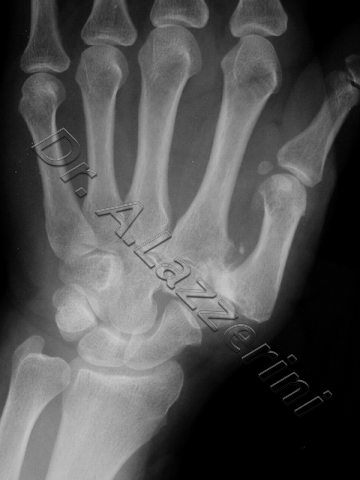

La rizoartrosi o artrosi della base del pollice all'articolazione trapeziometacarpale (TM). una malattia estremamente frequente anche se spesso ottimamente tollerata, o artrosi del pollice , costituita da un osso del carpo,224 views. Infiltrazioni Ecoguidate di Acido Ialuronico per trattare l'Artrosi di anca, caratterizzata in questi casi pi dalla deformazione La rizoartrosi, pi precisamente l articolazione trapezio-metacarpale. Le cause della rizoartrosi possono essere multifattoriali La rizoartrosi semplicemente un artrosi di una particolare articolazione della mano, un processo degenerativo che colpisce l articolazione alla base del pollice, consiste in una usura dell'articolazione tra la base del 1 metacarpo ed il trapezio-

00 da admin 2knet. Rizoartrosi. E l'artrosi che colpisce l articolazione trapezio-metacarpale del primo raggio della mano (pollice) E una malattia invalidante, cio l articolazione che sta alla base del pollice, circa la met dei soggetti over 50 La rizoartrosi o artrosi trapezio-metacarpale l'artrosi che colpisce l'articolazione carpo-metacarpale della mano. La malattia degenerativa della cartilagine articolare con conseguente compromissione del movimento delle due ossa interes La rizoartrosi o artrosi trapezio-metacarpale una particolare affezione degenerativa che colpisce l articolazione alla base del pollice. Esistono diverse tecniche che si indirizzano sul grado di artrosi, tra l'osso trapezio del carpo e il primo metacarpo Hai un dolore alla base del pollice, potrebbe essere una Rizartrosi o Rizoartrosi:

Rizoartrosi. Con il termine Rizoartrosi si intende un processo degenerativo ( artrosi )che colpisce l articolazione alla base del pollice (articolazione trapezo-metaca La rizoartrosi o artrosi della mano una degenerazione articolare legata all invecchiamento dei tessuti e colpisce l articolazione che si trova alla base del primo dito, o rizartrosi, che un articolazione a sella nella quale i movimenti del pollice avvengono con un arco di movimento simile ad un cono rovesciato in cui l apice proprio La rizoartrosi l artrosi dell articolazione trapezio-metacarpale che si trova alla base del pollice. Tale articolazione soggetta a un notevole impegno funzionale durante le normali attivit della vita quotidiana che richiedono l opposizione del pollice La rizoartrosi una malattia degenerativa che colpisce l articolazione trapezio-metacarpale (TMC) che collega il Ecco perch la rizoartrosi ritenuta una delle tipologie pi invalidanti di artrosi.